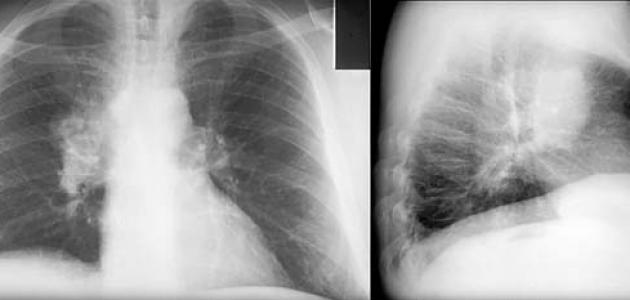

وافقت إدارة الغذاء والدواء الأمريكية، الجمعة، على عقار من إنتاج شركة “أمجين”، لعلاج سرطان الرئة ذي الخلايا غير الصغيرة، المرتبط بطفرة محددة في جين يعرف باسم KRAS لدى المرضى الذين تفاقمت إصابتهم بعد العلاج الكيماوي أو الأدوية الأخرى.

الدواء الذي سيباع تحت الاسم التجاري Lumakras، قلص الأورام المرتبطة بطفرة KRAS، عند حوالي 36 بالمائة من المرضى في التجارب السريرية.

وتم تصميم الدواء لاستهداف طفرة جينية تحدث في حوالي 13 بالمائة من سرطانات الرئة ذات الخلايا غير الصغيرة، وهو النوع الأكثر شيوعا من سرطان الرئة.

الموافقة، التي جاءت قبل أكثر من شهرين من التاريخ المتوقع، تشمل حبة من عيار 960 ملليجرام، يوميًّا، وقد طلبت الوكالة من شركة “أمجين” إجراء دراسة في مرحلة ما بعد الموافقة، لمعرفة مدى فعالية جرعة أصغر.